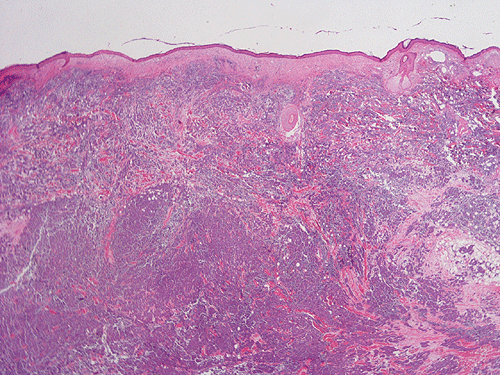

The mass appears to be a subcutaneous tumor that spares the dermis and epidermis (Panel A). On scanning magnification, the tumor has a infiltrative growth pattern (Panel B). Intrestingly, the tumor does not really invade into the parotid gland (Panel C). On medium magnification, the tumor cells arrange in irregular islands with a solid pattern (Panel D). On high magnification, the tumor cells have medium sized large nuclei with high nuclear to cytoplasmic ratio (Panel E) and scant amount of cytoplasm. The cytoplasmic membrane is not distinct. The nuclei have a coarse salt and pepper like pattern and without prominent nucleoli. On immunohistochemistry, strongly positive expression of CK20 in terms of dots are present in many of the tumor cells (Panel F). A similar but stronger staining pattern with antibodies against neurofilament proteins (Panel G).  The tumor cells are also positive for synaptophysin (Panel H).

Histologically, MCC is a dermal based tumor. Histological features often typify that of small, round blue cell tumors. The cells have very high nuclear cytpplasmic ratio, hyperchromatic nuclei with evenly distributed chromatin without prominent nucleoli. Mitotic figures are common. The tumor is characteristically separated from the epidermis by a "grenz" zone. It can be morpholgoically classified into three subtypes, namely the small cell type, the trabecular type and the intermediate type.